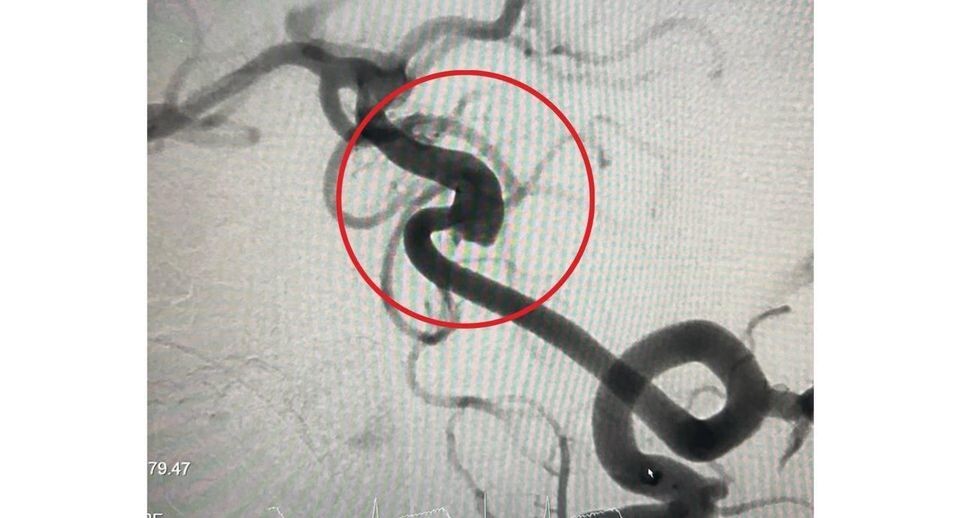

Специалисты Детского клинического центра имени Л. М. Рошаля спасли девятилетнего пациента с редкой аневризмой сосудов головного мозга. Патология могла привести к инсульту.

«Мы выполнили мальчику операцию с применением современных технологий имплантации поток-перенаправляющего стента. В ходе рентгенэндоваскулярного вмешательства через бедренную артерию мы провели катетер к сосудам головного мозга и разместили имплант в области аневризмы», — рассказал заведующий отделением рентгенэндоваскулярных методов диагностики и лечения Михаил Комиссаров.